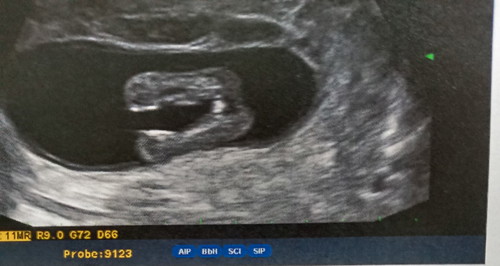

ซาวดูเมื่อวาน16wไม่แน่ใจว่าเพศอะไร

แม่ๆช่วยดูหน่อยค่ะว่าเหมือนจิมิหรือจุดจู๋พอดีหมอบอกยังดูเพศไม่ออก นัดซาวเพศวันที่28นี้ แต่ตื่นเต้นมากเลยเดาๆเอากันเองค่ะ ?

เหมือนจะญ.นะคะ รอหมอคอนเฟิร์มอีกที

คล้ายผู้หญิงค่ะ